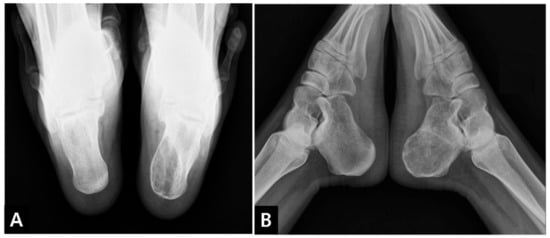

2. Case Presentation

2.1. Preoperative Evaluation